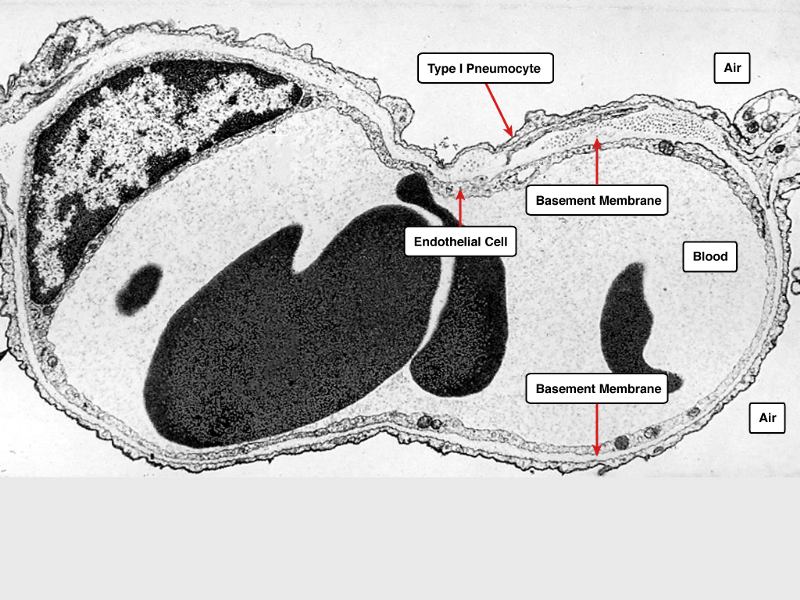

Go with the flow

Trace the air flow of respiratory system starting with the nostrils.

What path does a molecule of oxygen take to reach the blood?

Path of O2

• List complete

• With layers

• And cells

• And function of each

• By studying and labelling images